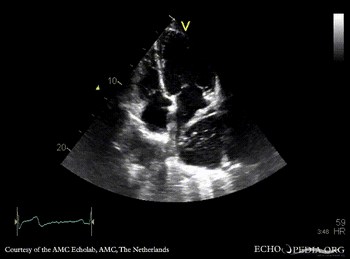

| A4CH | A4CH color doppler |